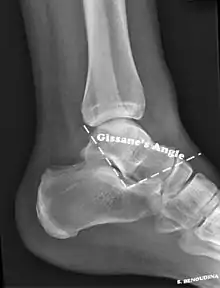

| X-ray of a fractured calcaneus | |

The Angle of Gissane, or "Critical Angle", is the angle formed by the downward and upward slopes of the calcaneal superior surface. On a lateral radiograph, an angle of Gissane > 130° suggests fracture of the posterior subtalar joint surface. Böhler's angle, or the "Tuber Angle", is another normal anatomic landmark seen in lateral radiographs. It is formed by the intersection of 1) a line from the highest point of the posterior articular facet to the highest point of the posterior tuberosity, and 2) a line from the former to the highest point on the anterior articular facet. Böhler's angle is normally 25° to 40°.[14] It is named after Austrian physician Lorenz Böhler.[16] A decreased angle is indicative of a calcaneal fracture.